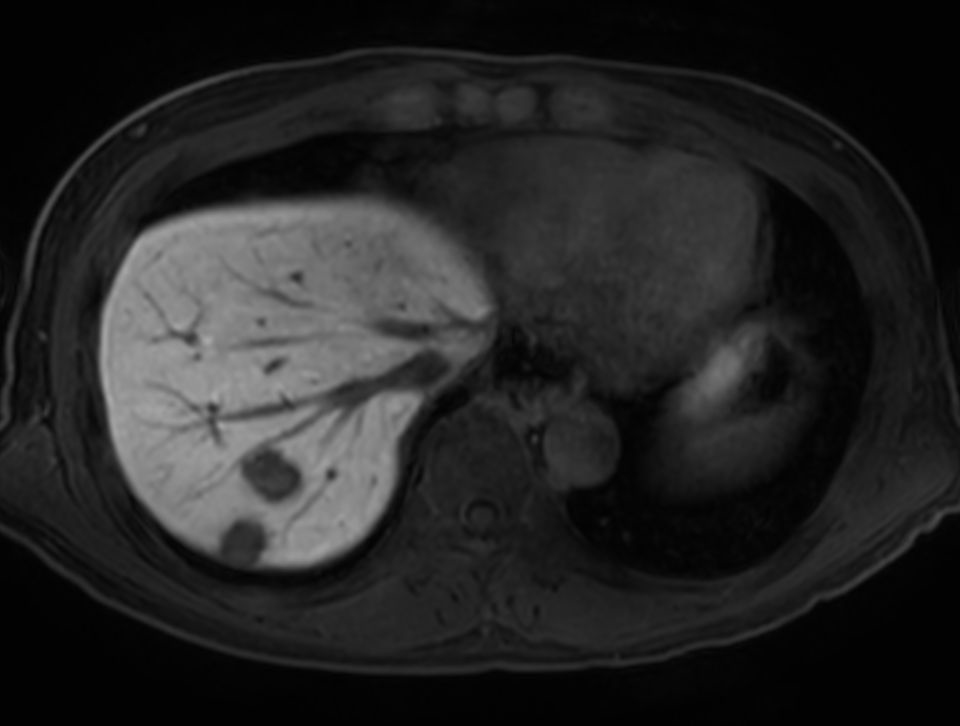

mDIXON Quant (fat percentage) - Breath hold

Patient with liver metastasis. ExamCard includes Compressed SENSE to shorten the breath hold time, VitalEye for touchless respiratory sensing, mDIXON Quant for non-invasive liver fat fraction quantification and 4D FreeBreathing to perform multi-phase contrast-enhanced MRI studies.